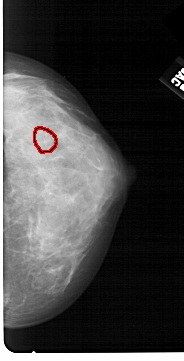

A_1345_1.RIGHT_MLO

LEFT_MLO LINES 4846 PIXELS_PER_LINE 2356 BITS_PER_PIXEL 12 RESOLUTION 43.5 NON_OVERLAY

FILE: A_1345_1.RIGHT_MLO.OVERLAY

TOTAL_ABNORMALITIES 1

ABNORMALITY 1

LESION_TYPE CALCIFICATION TYPE PLEOMORPHIC DISTRIBUTION CLUSTERED

ASSESSMENT 4

SUBTLETY 4

PATHOLOGY BENIGN

TOTAL_OUTLINES 1

BOUNDARY